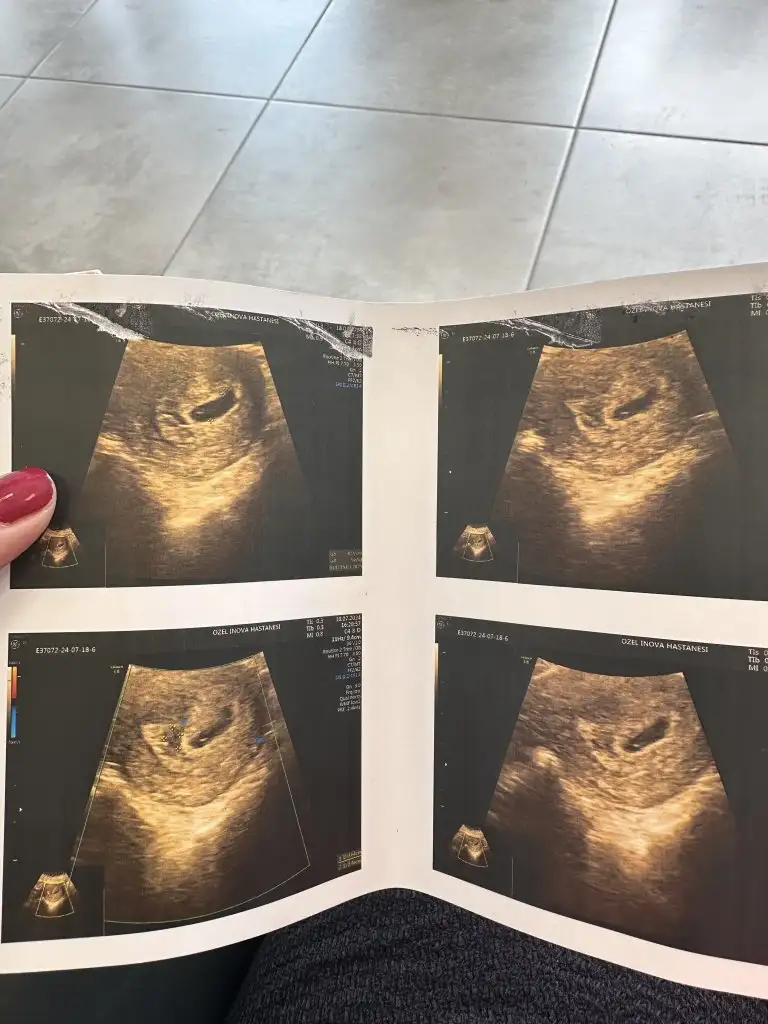

Yavrum kesen gayet güzel maşallah minnoş da belli ediyo kendini sakın üzme. Bak bende de kist varmış. Nolcak diyorum bişe olmicak doğurcan gitcek dedi. Canım sıkıldı ama kanama falan yaparsa yapcak bişe yok dedim. O kanama alanı küçüle de bilir hiç belli olmaz sakın üzülme sen al iznini yat dinlen iş bile yapma. Bol bol dua et bebeğimKuşum bugun agrım oldu dr a gıttık normalde cumartrsıydı randevu kese bebek yolk hepsı cok guzel olusmus ama kanama alanı var dedı doktor dusuk tehdıtı varmıs cok uzuldum progestron verdı fıtıl olarak tam olarak nasıl kullancam yazarmısınız bana.o kdar uzuldumkı sormayı unuttum lekelenmem neden yok dedım kanama ıcerde kesenın yanında dedı,bı bakın cokmu buyuk kanama bısey olurmu?yıllık ıznımı alcam ıkı hafta daha dınlencem evdedestinesiaa melegim can

Canım büyük degil kanama alanın benimki bundan büyüktü ilk 3 ay progesteron fitil kullandım sabah akşam vajinadan agızdan alma vajina daha etkili yat dinlen yenek ve lavabo dışında kalkma hemen geçer inşallah korkmaKuşum bugun agrım oldu dr a gıttık normalde cumartrsıydı randevu kese bebek yolk hepsı cok guzel olusmus ama kanama alanı var dedı doktor dusuk tehdıtı varmıs cok uzuldum progestron verdı fıtıl olarak tam olarak nasıl kullancam yazarmısınız bana.o kdar uzuldumkı sormayı unuttum lekelenmem neden yok dedım kanama ıcerde kesenın yanında dedı,bı bakın cokmu buyuk kanama bısey olurmu?yıllık ıznımı alcam ıkı hafta daha dınlencem evdedestinesiaa melegim can